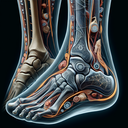

МРТ гомілково-ступневогу суглобу

Магнітно-резонансна томографія (МРТ) гомілково-ступневого суглобу – це неінвазивний метод діагностики, що дозволяє отримати детальні зображення м'яких тканин, хрящів, зв'язок, сухожиль і кісток. Цей метод дуже корисний для виявлення травм, запальних процесів або дегенеративних змін. Показання для проведення МРТ гомілково-ступневого суглобу можуть включати: 1...